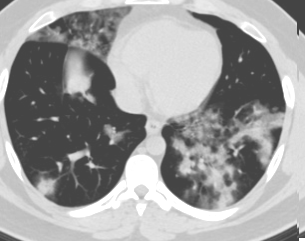

SARS-CoV-2 CT Scan dataset [50]: The dataset was collected from hospitals of Sao Paulo, Brazil, with a total of 2482 CT scans acquired from 120 patients of both genders. It is composed of 1252 scans for patients infected with SARS-CoV-2 and 1230 scans for patients infected with other lung diseases. The CT scans have varying spatial sizes between and , and are available in PNG format. CT scans from this dataset are shown in Figure 7.

COVID19-CT dataset [51]: The dataset consists of a total of 746 CT images. There are 349 CT images of patients with COVID-19 and 397 CT images showing Non-COVID-19, but other pulmonary diseases. The positive CT images were collected from preprints about COVID-19 on medRxiv and bioRxiv, and they feature various manifestations of COVID-19. Since the CT images were taken from different sources, they have varying sizes between and . Figure 8 shows example CT images from the COVID19-CT dataset.

On the COVID19-CT dataset, the overall performance with respect to all evaluation metrics is inferior to that on the SARS-CoV-2 dataset. This can be attributed to the cross-source heterogeneity of the CT images in the dataset. The Non-COVID-19 CT images were taken from different sources and show diverse findings which pose difficulty to distinguish between COVID-19 and other findings associated with lung diseases due to the potential overlap of visual manifestations (see Figure 8). Another reason is that, the CT images in the COVID19-CT dataset show strong variations in contrast, variable spatial resolution and other visual characteristics, which could affect the model’s ability to extract more discriminative and generalizable features.